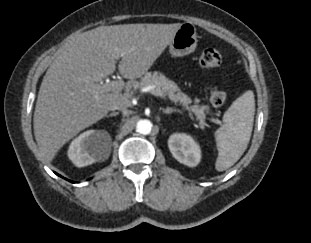

Современным высокоинформативным способом выявления патологических изменений поджелудочной железы является мультиспиральная компьютерная томография с прицельным сканированием органа. Метод КТ основан на применении рентгеновского излучения и способности органов и тканей поглощать рентгеновские лучи.

При необходимости детальной визуализации структуры железы, особенно в случае подозрения на развитие опухоли, назначается КТ поджелудочной железы с контрастом. Для этого применяются йодсодержащие контрастные препараты, которые вводятся пациенту внутривенно. Контрастное вещество, попадая в кровоток, контрастирует кровеносные сосуды и патологические очаги на фоне окружающих здоровых тканей.

Контрастирование позволяет отличить зоны воспаления, деструкции, разрастания фиброзной ткани и опухолевой трансформации от сохраненной паренхимы поджелудочной железы. КТ поджелудочной железы с контрастированием дает исчерпывающую информацию о состоянии органа и патологических процессах в нем.

При помощи специальных цифровых приложений данные, полученные при сканировании, преобразуются в трехмерные изображения органа, что дополнительно повышает точность и достоверность диагностики заболеваний поджелудочной железы.